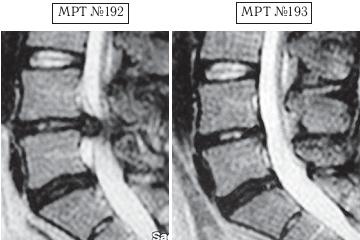

Пример № 1.

На МРТ № 192 наблюдается состояние поясничного отдела позвоночника: рецидив после операции — секвестрированная грыжа межпозвонкового диска в сегменте LIV-LV, абсолютный стеноз спинномозгового канала.

На МРТ № 193 — состояние поясничного отдела позвоночника после лечения методом вертеброревитологии.